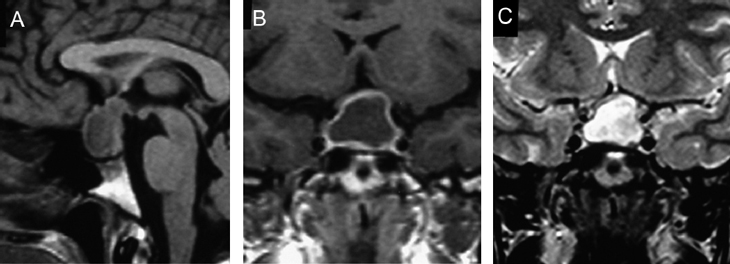

Figura 3A. Corte sagital, secuencia T1w. Glándula pituitaria en un recién nacido, muestra hiperseñal homogénea normal a esta edad.

Figura 3B. Corte sagital, secuencia T1w. Glándula pituitaria en lactante de 2 meses, muestra disminución de la hiperseñal de la adenohipófisis.

Figura 4A. Corte sagital, secuencia T1w. Glándula pituitaria normal en adulto joven (27 años), muestra foco posterior de hiperseñal de la neurohipófisis (punta de flecha); la señal de la adenohipófisis es similar a la de la protuberancia.

Figura 4B. Corte sagital, secuencia T2w.en el mismo paciente, la glándula pituitaria, muestra la neurohipófisis con leve hiperseñal (punta de flecha); la señal de la adenohipófisis es también similar a la protuberancia en esta secuencia.

Figura 4C. Corte sagital, secuencia T1w post inyección de Gadolinio. La glándula pituitaria, muestra refuerzo normal incluyendo el tallo pituitario; en el cerebro solo se refuerzan las estructuras vasculares.

Figura 5. Corte sagital, secuencia T1w. Examen realizado dos días postparto; muestra la pituitaria levemente mas intensa que la protuberancia, con un borde superior convexo (puntas de flecha), que ocupa la porción central inferior de la cisterna supraselar, lo que corresponde a hallazgos normales en esta condición.